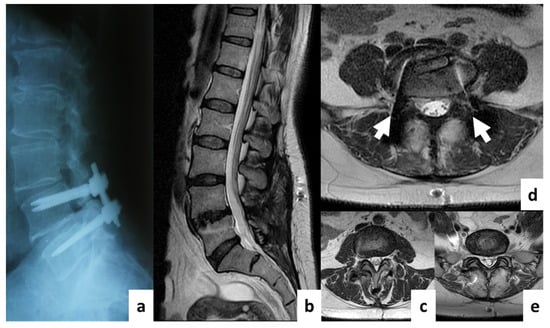

Comparison of MRI Visualization Following Minimally Invasive and Open TLIF: A Retrospective Single-Center Study

3. Results